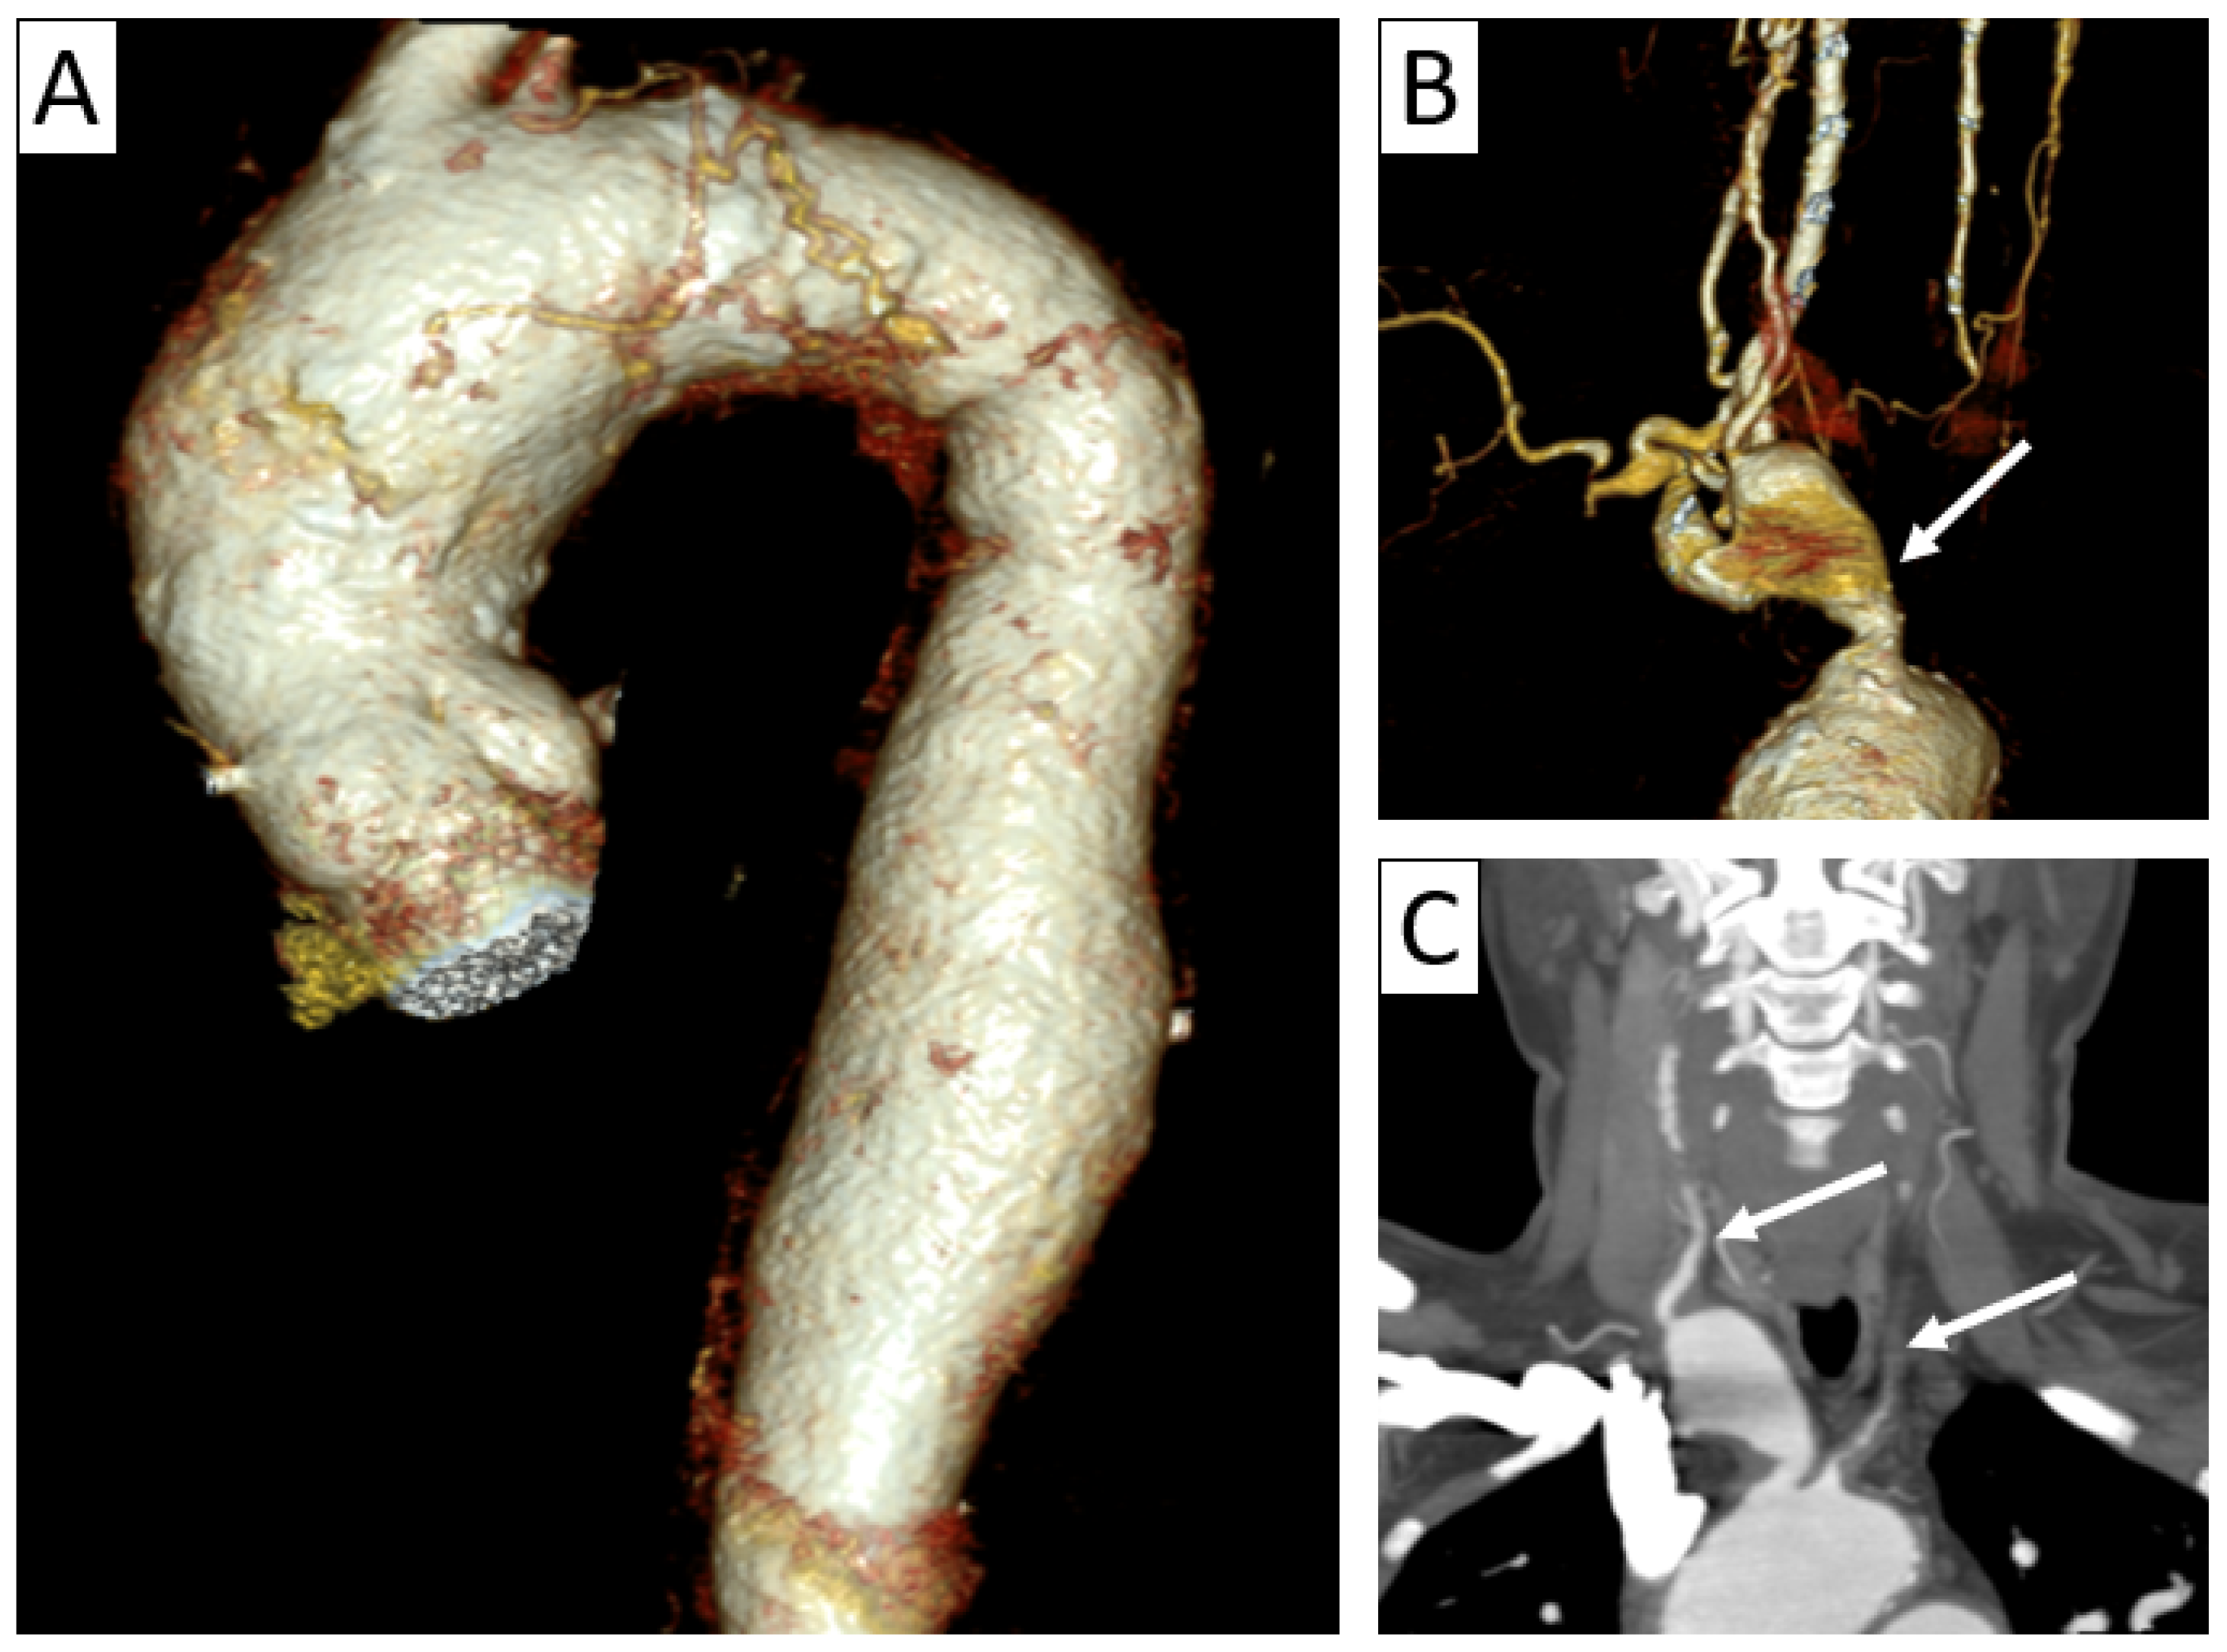

| CTA | Circumferential parietal thickening Vessel wall enhancement | Circumferential parietal thickening Vessel wall enhancement Luminal stenosis or narrowing |